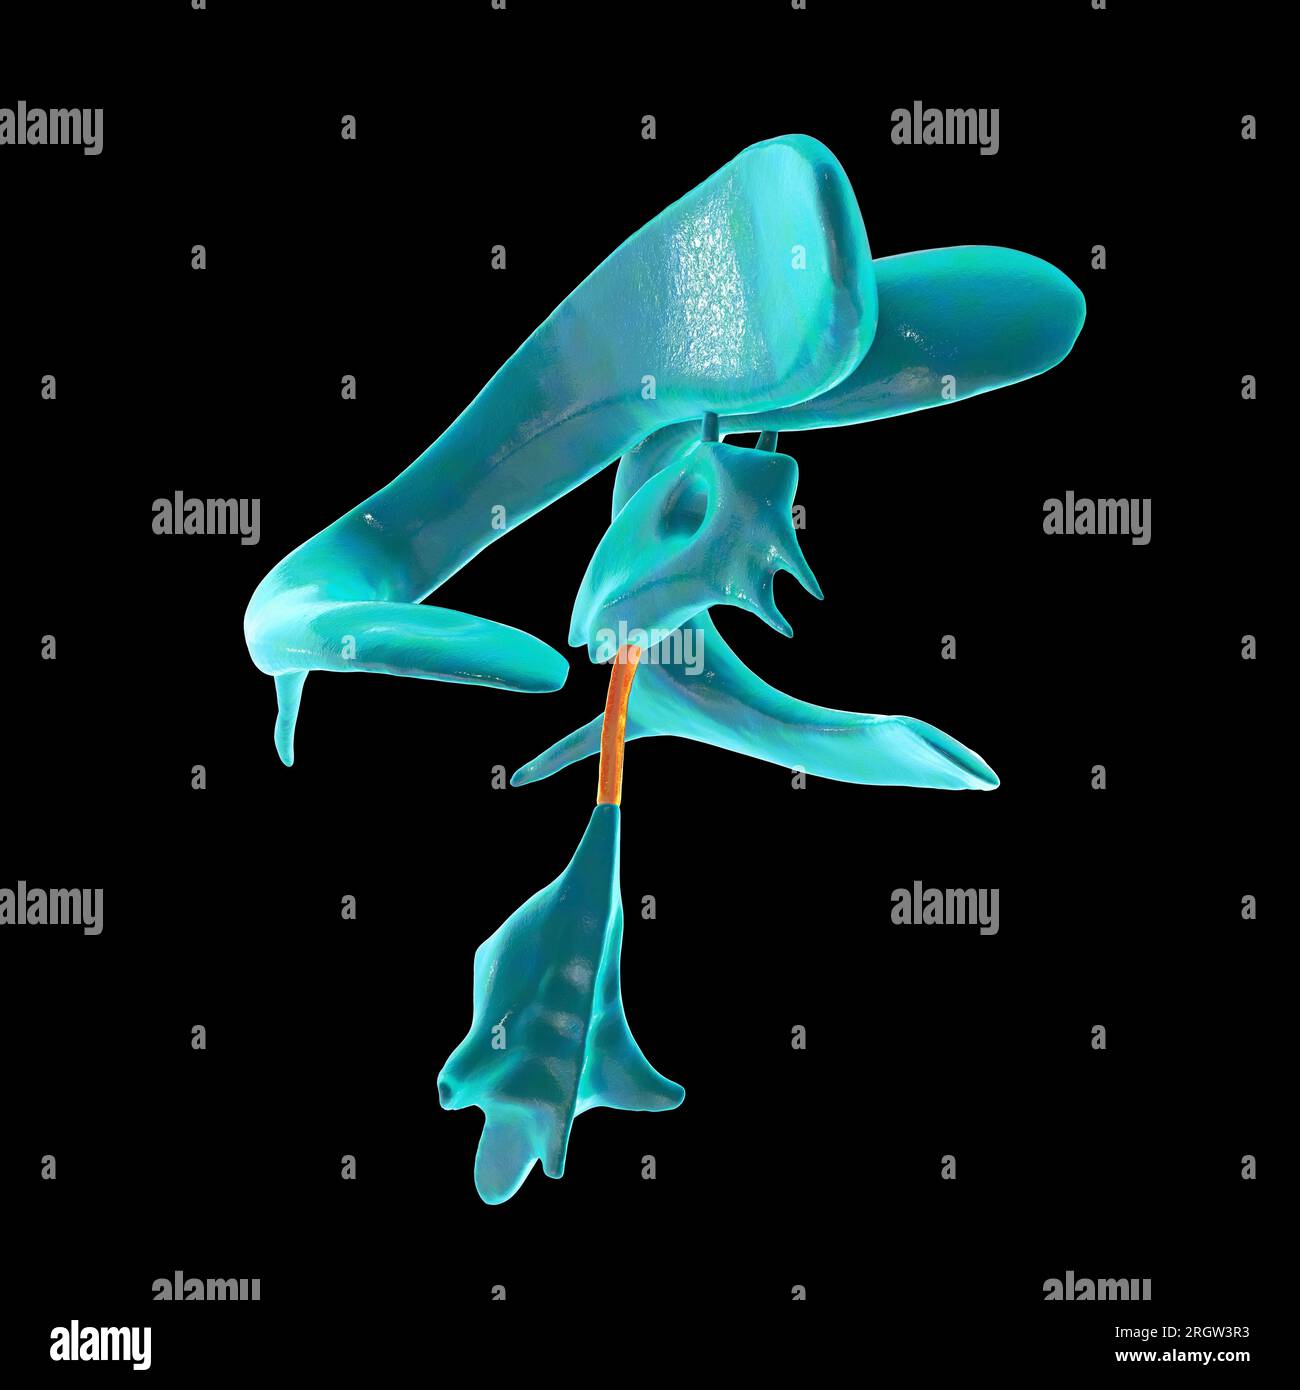

RM2AWF8JC–Die Anatomie des Nervensystems, vom Standpunkt der Entwicklung und Funktion. -Ant. HornCentra, Teil Latcral vnnInf. Horn Q virale Pari Ant. Horn. Ventrikel Ventrikel Ventrikel Ventrikel Ventrikel Ventrikel Ventrikel Ventrikel Ventrikel Ventrikel Ventrikel Ventrikel Ventrikel Ventrikel Ventrikel Ventrikel Ventrikel Ventrikel Ventrikel Ventrikel ^^ 176.-Zwei Ansichten der Hirnventrikel des Menschen: A, Dorsale Ansicht; B, laterale Ansicht. Das Vorderhorn oder Cornu anterius ist der Teil, der rostral zum interventrikulären Foramen liegt. Seine Dach- und Rostrallgrenze wird von Thecorpus callosum gebildet. Sein mediales

RM2AWFNN9–Menschliche Anatomie, einschließlich Struktur und Entwicklung und praktische Überlegungen d in einem sagittalen mesialen Abschnitt (Abb. 910) wird jede dieser Teilungen als mit einem Teil des Systems der Kommunikation von Räumen verwandt angesehen, die als die dritten Ventrikel des Lateralands, der Aquädukt von Sylvius und der vierte Ventrikel die oben genannten Gehirnhemisphären ausdehnen. Durch den Hirnstamm und unter dem Kleinhirn bis zum zentralen Kanal des Rückenmarks. Da die lateralen Ventrikel zwei innumerieren, ist die Theirstellung im Zusammenhang mit den Gehirnhemisphären, in denen sie liegen, lateral zum m

RM2AN4TWY–Handbuch der allgemeinen, beschreibenden und pathologische Anatomie (Band 2). Ventrikel, ein. Ventrikel des Kleinhirns, b. Aquädukt von Sylvius, C. Dritten Ventrikel, d. Lateralen Ventrikel, 1. Vordere Horn, 2. Hintere Horn, 3. Absteigend Horn, II. Textur, III. Gewicht, IV. Konsistenz, Kap. Iii. Umhüllt des Gehirns. Abt. Ich. Pia - mater, I. des Rückenmarks, II. Von Hirn, ein. - Externe Pia mater, b. Interne pia-mater, ich. Choroid Plexus des vierten Ventrikel, ii. Choroid Plexus des Großhirns, Art.ii.Apert-syndrom Membran, Art. hi. Dura-mater, I. spinalen Dura-mater, II. Zerebrale Dura-mater